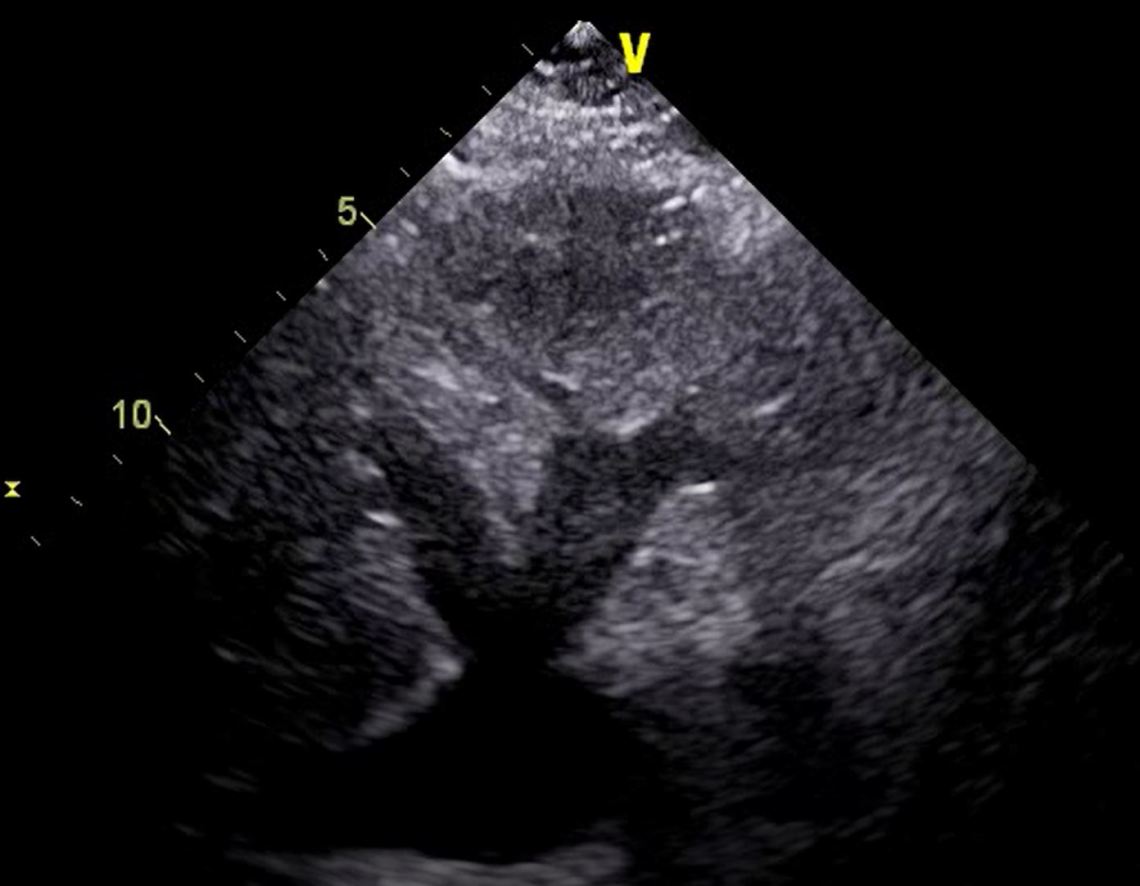

Bedside ultrasound was performed:

That left atrium looks big. Sometimes an off angle PLAX slice can make the LA look bigger than it truly is. However note that this slice seems reasonable in that it is on axis, and both the MV and AV are visible. In practice I actually checked my probe positioning and tried a rib space higher as well.

The classic D sign, indicative of R heart strain. Note the RV looks big as well – it’s not normally that prominent at the level of the papilla.

Apical views are notorious for exaggerating the size of atria depending on how the slice cuts through the patient. However, this view is on axis (probe at apex). That was the largest I could get the LA to appear. Even then the RA looks very enlarged (it’s usually smaller than the LA). During diastole (MV snaps open), note how the atrial septum pushes into the LA. That suggests some serious right heart strain.

You cannot overestimate the size of the RA on a subcostal window.

This patient had a gastric bubble overlying zis heart, and this view was obtained with difficulty. The RA was obviously enlarged.